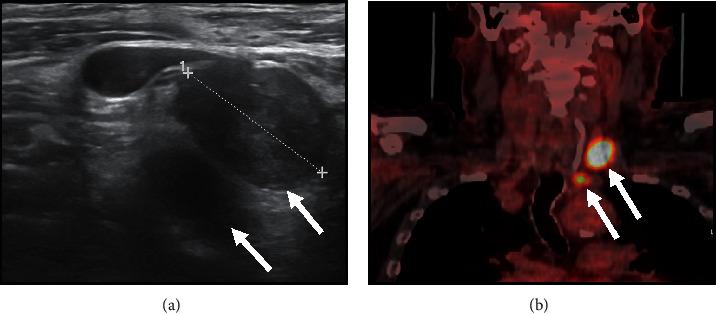

Over 50% of patients with papillary thyroid carcinoma (PTC) have cervical lymph-node metastasis on diagnosis, and up to 30% show nodal recurrence after surgery plus radioactive iodine (131I) (RAI) therapy. The combination of ultrasonography (US) and fine-needle aspiration cytology (FNAC) and the measurement of thyroglobulin (Tg) in washout fluid are cornerstones in the diagnosis of nodal metastasis. In the absence of anti-Tg antibodies, unstimulated serum thyroglobulin (Tg) levels are generally a reliable marker of recurrent disease, and 18F-FDG positron emission tomography (PET)/computed tomography (CT) plays an important role in the imaging work-up. We report the case of a 65-year-old man evaluated for a large multinodular goitre which caused compressive symptoms; the dominant nodule in the left lobe presented suspicious features on US. Thyroid function showed subclinical hypothyroidism, calcitonin was normal, serum thyroglobulin levels were low, and anti-thyroid antibodies were absent. The prevalent left nodule showed an intense uptake on 18F-FDG PET/CT but proved benign at FNAC. On the basis of the suspicious clinical and imaging features, total thyroidectomy was performed. Histology revealed a tall-cell variant of PTC with scattered expression of Tg and diffuse high expression of cytokeratin (CK) 19; RAI therapy was performed. Within 6 years of surgery, left laterocervical lymph-node recurrence was twice detected (first at levels II and III, then at levels IV and VI) by US and 18F-FDG-PET/CT and was confirmed by FNAC. Tg levels in the washout fluid proved clearly diagnostic of metastasis only in the second, larger, recurrence, whereas serum Tg levels (in the absence of anti-Tg antibodies) always remained undetectable on L-thyroxine therapy. Surgery was performed on both recurrences, and histology confirmed lymph-node metastasis of PTC. Immunohistochemical expression of Tg and CK 19 was similar to that of the primary tumour. No further relapses have occurred to date. Posttherapy (surgery and RAI) unstimulated serum Tg levels may not be a reliable marker of nodal recurrence in patients with differentiated thyroid cancer (DTC) that produces low amounts of Tg.

超过50%的甲状腺乳头状癌(PTC)患者在诊断时已有颈部淋巴结转移,高达30%的患者在手术加放射性碘(131I)(RAI)治疗后出现淋巴结复发。超声检查(US)、细针穿刺细胞学检查(FNAC)以及冲洗液中甲状腺球蛋白(Tg)的检测相结合,是诊断淋巴结转移的基石。在不存在抗Tg抗体的情况下,未刺激血清甲状腺球蛋白(Tg)水平通常是复发疾病的可靠标志物,18F-FDG正电子发射断层扫描(PET)/计算机断层扫描(CT)在影像学检查中发挥着重要作用。我们报告了一例65岁男性患者,因巨大结节性甲状腺肿出现压迫症状而接受评估;左叶的优势结节在超声检查中呈现可疑特征。甲状腺功能显示亚临床甲状腺功能减退,降钙素正常,血清甲状腺球蛋白水平低,且无抗甲状腺抗体。优势的左侧结节在18F-FDG PET/CT上显示摄取增强,但在FNAC检查中被证明为良性。基于可疑的临床和影像学特征,进行了全甲状腺切除术。组织学检查显示为PTC的高细胞变体,Tg呈散在表达,细胞角蛋白(CK)19呈弥漫性高表达;进行了RAI治疗。在手术后6年内,通过超声检查和18F-FDG-PET/CT两次检测到左侧颈外侧淋巴结复发(首次在Ⅱ区和Ⅲ区,随后在Ⅳ区和Ⅵ区),并经FNAC证实。冲洗液中的Tg水平仅在第二次较大的复发中明确诊断为转移,而在左甲状腺素治疗期间,血清Tg水平(在不存在抗Tg抗体的情况下)始终未被检测到。对两次复发均进行了手术,组织学检查证实为PTC的淋巴结转移。Tg和CK 19的免疫组化表达与原发肿瘤相似。迄今为止未再发生复发。在分化型甲状腺癌(DTC)产生少量Tg的患者中,治疗后(手术和RAI)未刺激血清Tg水平可能不是淋巴结复发的可靠标志物。